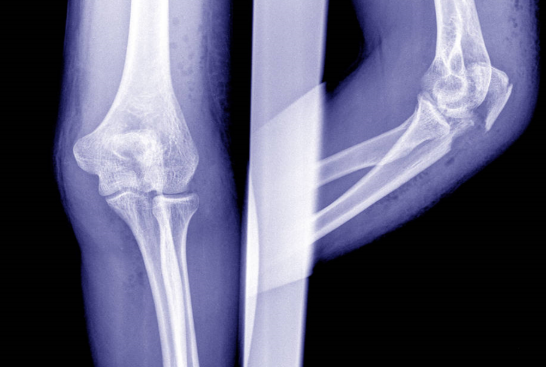

这天小孙陪客户喝完酒 , 酒过三巡的他走路摇摇晃晃的 , 不小心踩空从饭店台阶上摔下 , 当时腿疼的都不敢动 , 合伙人立马叫救护车把他送到医院 。 经检查 , 小孙右腿股骨颈骨折 , 需要手术治疗 , 医生建议他再做个骨密度检测 , 结果骨密度偏离正常值5.1 , 这属于中度骨质疏松患者了 , 怪不得这么年轻摔一下能骨折 , 都是骨质疏松惹的祸 。

3.脆性骨折 , 骨折是最严重的并发症 , 受轻微外力就容易发生骨折 , 有的甚至用力咳两下 , 就导致胸椎的压缩性骨折 。